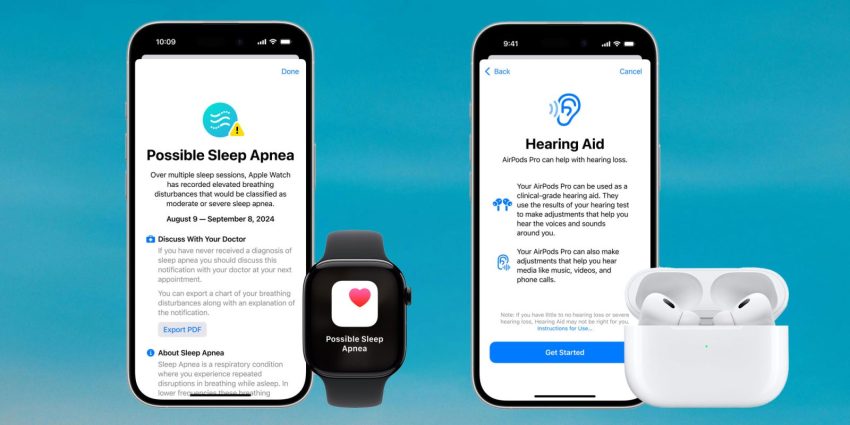

AirPods Pro 2 hearing features and Sleep Apnea alert now available in new countries